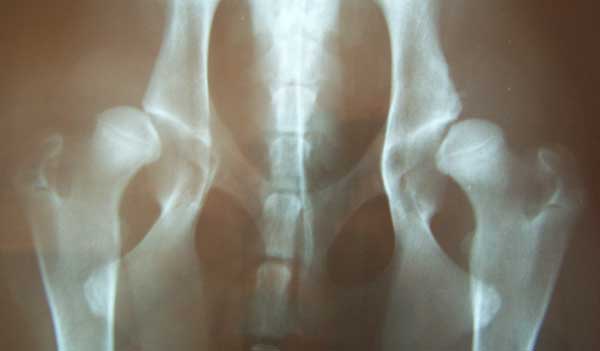

Cagne accoppiate poco più che cucciole, consanguineità stretta (e reiterata), riproduttori utilizzati con lastre per la displasia disastrose. Alcuni di questi li ho visti in expo, tra l’altro. Erano i primi tempi che era uscito il libro genealogico online, così quando vedevo sul ring qualche soggetto che camminava in modo un po’ strano me lo andavo a spulciare subito (parliamo di rottweiler). Displasie dell’anca con gradi C e D, e ovviamente già riprodotti. E prendevano Eccellente.